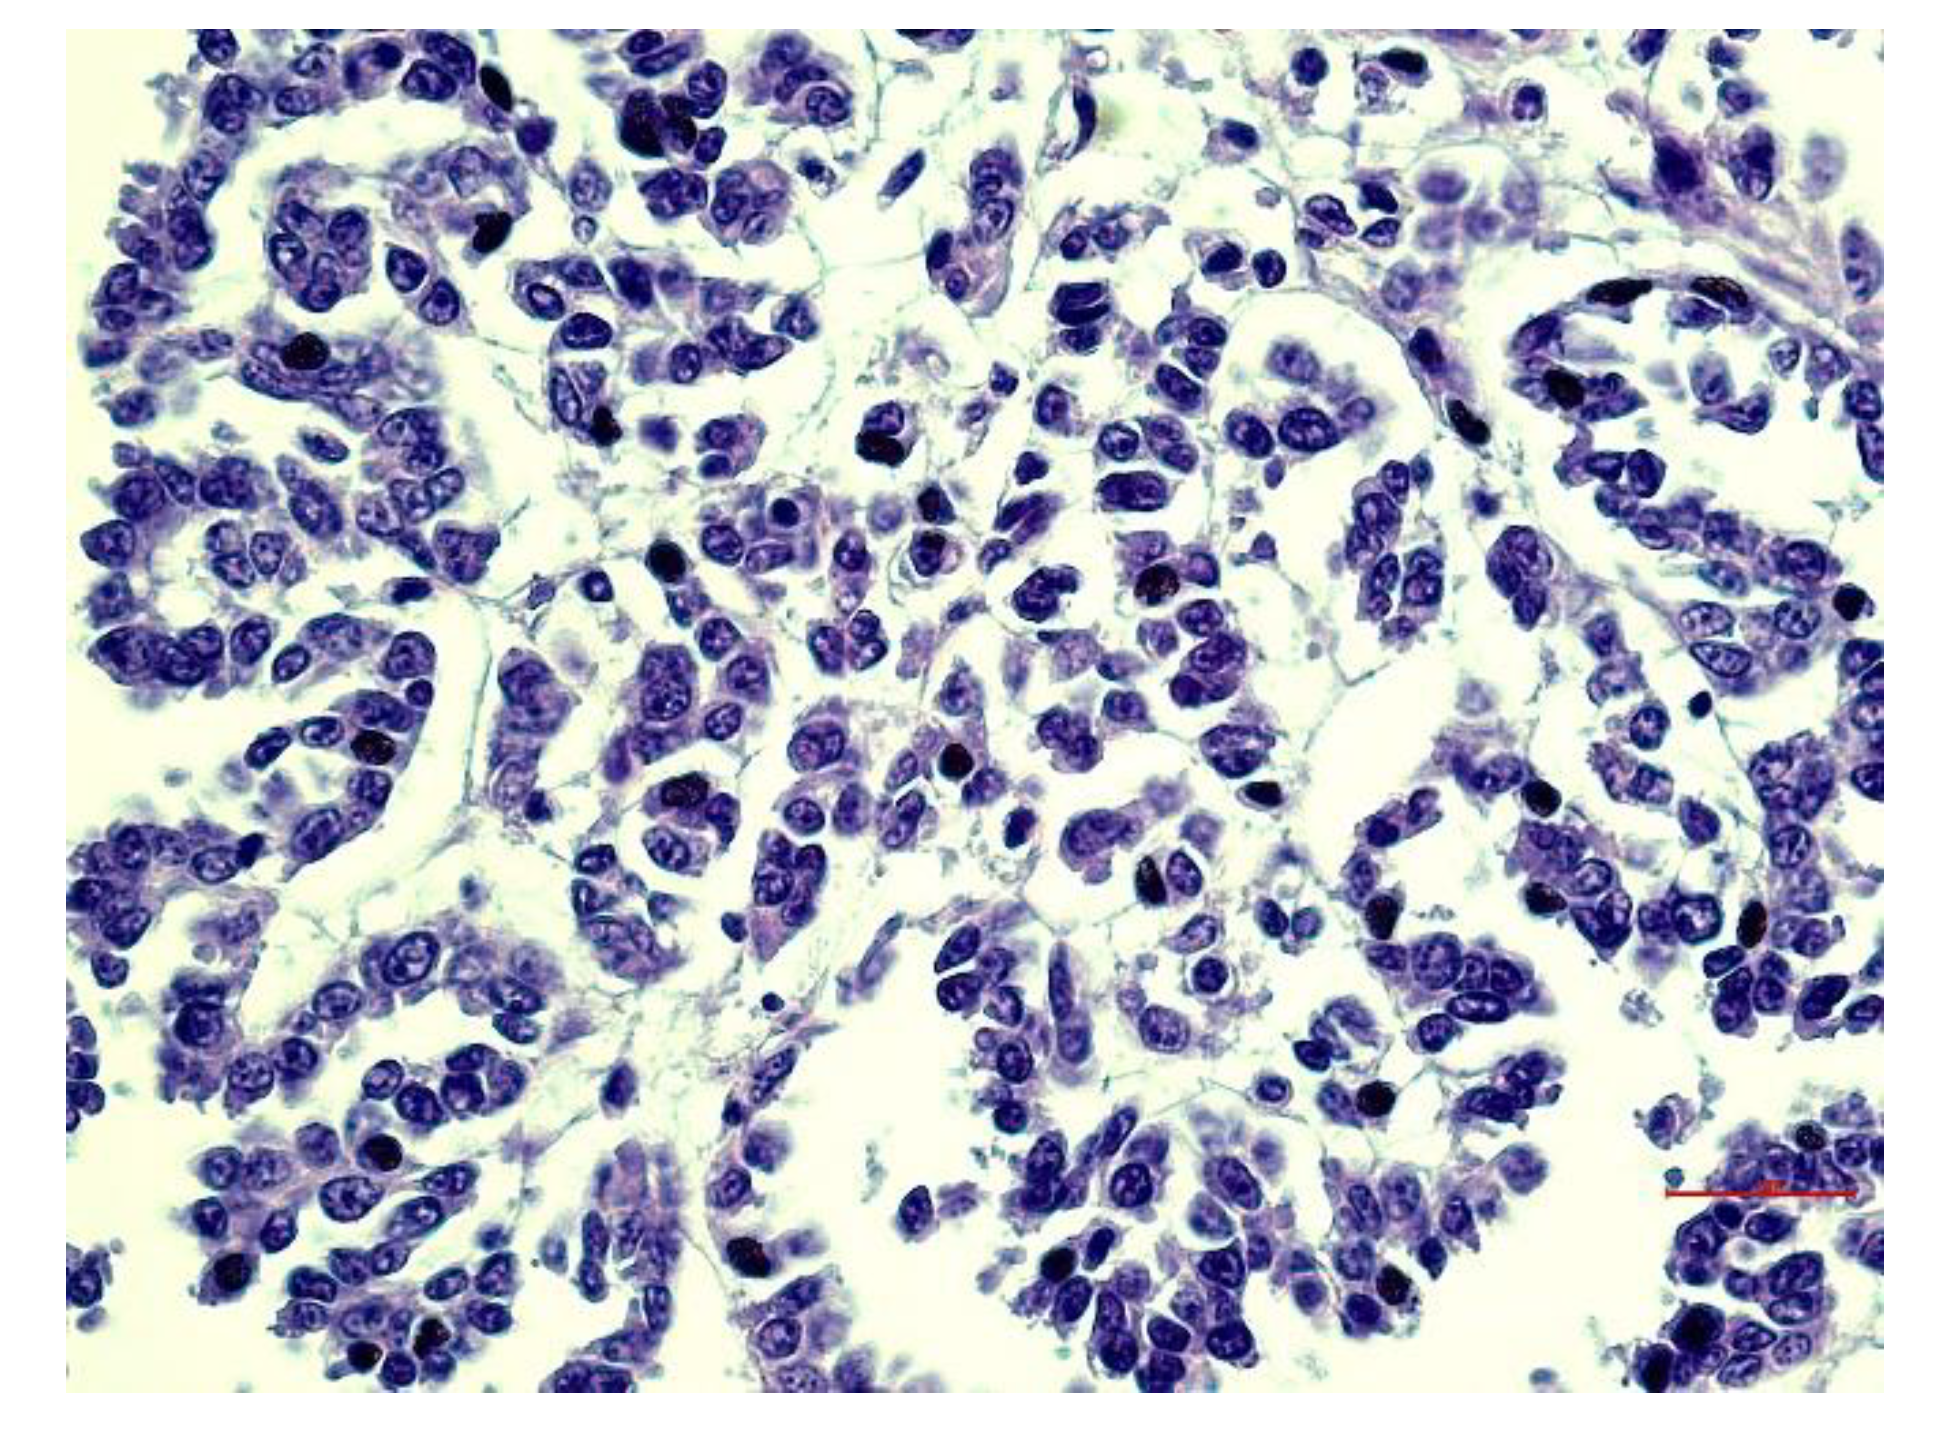

3.3. Histopathological Aspects

3.4. Immunohistochemical Aspects